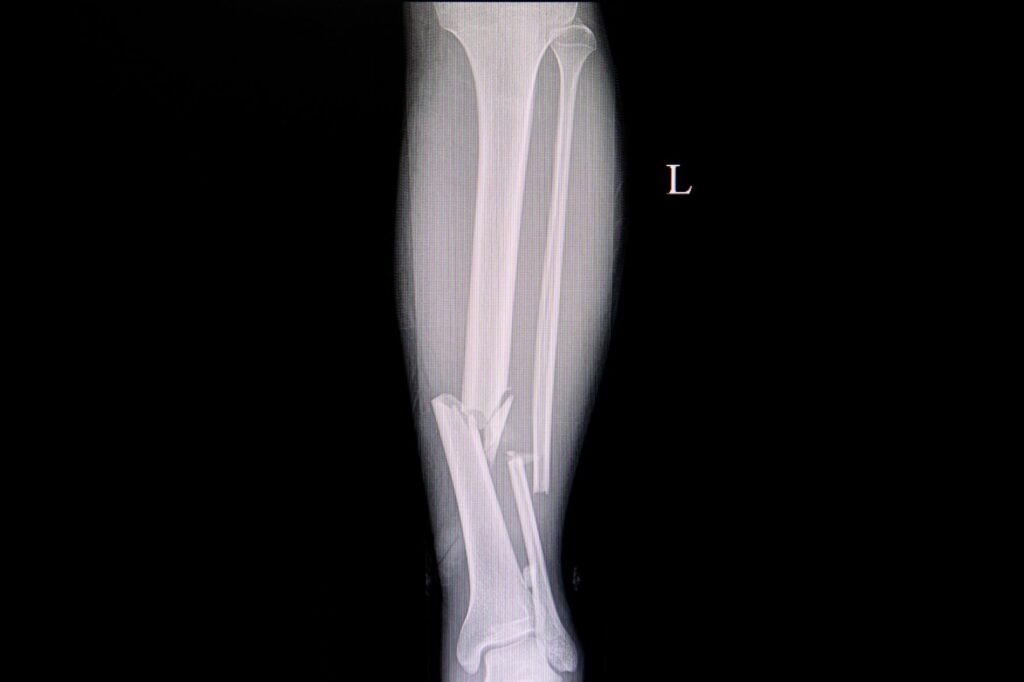

C. Złamania kości i stresowe złamania

- Złamania kości: Złamania kości nogi mogą być spowodowane urazami, przeciążeniem lub osteoporozą. Objawiają się silnym bólem, obrzękiem, trudnościami w poruszaniu się oraz ewentualnie zniekształceniem lub skróceniem kończyny.

- Stresowe złamania: Stresowe złamania to mikrozłamania kości, które wynikają z przeciążenia i nadmiernego obciążenia. Mogą występować u osób uprawiających sporty wymagające intensywnego wysiłku, jak bieganie długodystansowe. Objawiają się bólem stresowym, który nasila się podczas aktywności fizycznej.

B. Testy diagnostyczne: zdjęcia rentgenowskie, MRI, tomografia komputerowa

W celu lepszego zobrazowania struktur anatomicznych w nogach i wykluczenia lub potwierdzenia obecności urazu, deformacji lub innych zmian, lekarz może zlecić wykonanie różnych testów diagnostycznych. Zdjęcia rentgenowskie są powszechnie używane do wykrywania złamań, zwichnięć, zwyrodnień stawów czy zmian kostnych. MRI (magnetyczne rezonansowe badanie obrazowe) i tomografia komputerowa mogą dostarczyć bardziej szczegółowych obrazów tkanek miękkich i kości, umożliwiając identyfikację potencjalnych przyczyn bólu nogi, takich jak guzy czy zmiany zwyrodnieniowe.